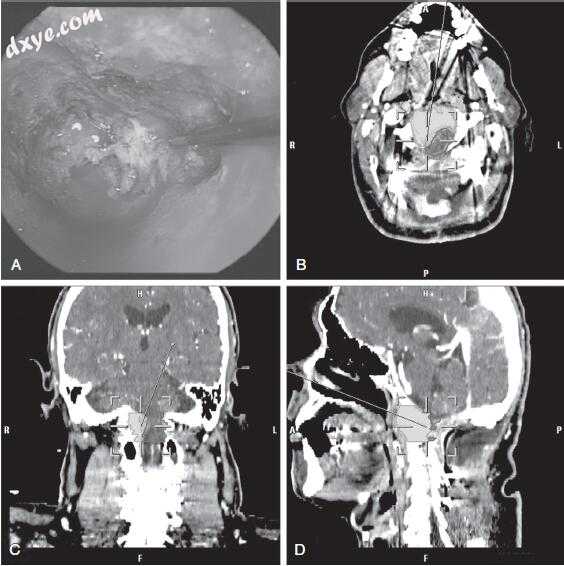

22.jpg

图-22. 术前(A)和术后(B)斜坡脊索瘤患者手术区域的轴向计算机断层扫描图像。 采用内镜辅助组合经鼻 - 经蝶窦 - 斜位手术入路。